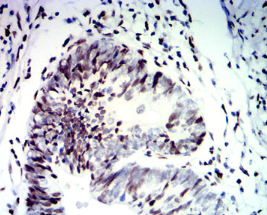

CDX2 Mouse Monoclonal antibody[5C11H]

IHC    1/200-1/1000